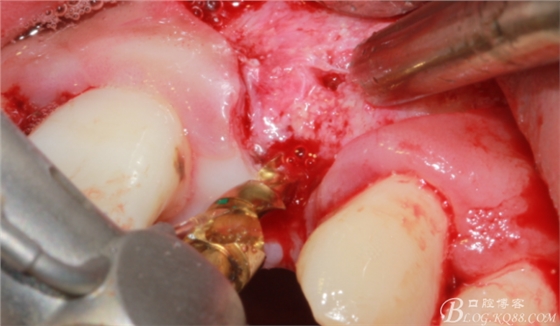

將自體骨與BIO-OOS骨粉混合植到術(shù)區(qū),蓋生物膜。

縫合。

4個(gè)月后,唇側(cè)豐滿度尚可,與鄰牙之間齦乳頭完整。

保留齦乳頭翻小瓣。

翻開后驚喜的發(fā)現(xiàn),術(shù)區(qū)成骨非常好,去除部分骨才暴露那顆長鈦釘。

取出影響種植入路的長鈦釘。